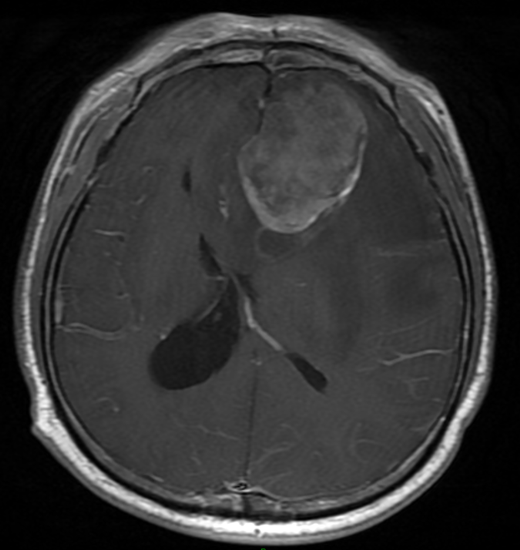

后顱底是神經(jīng)外科患病的高危部位。后顱底腫瘤不但引起頭痛、嘔吐等高顱壓癥狀,嚴(yán)重者誘發(fā)枕骨大孔疝等嚴(yán)重后果,治療不及時有猝死可能。春節(jié)前最后一個工作日,夏海堅主任醫(yī)師團(tuán)隊收治一急診病患,該患者系護(hù)理專業(yè)的在校大學(xué)生,因頭痛進(jìn)行性加重二月、頻繁惡心嘔吐一周入院?;颊呒韧鶑奈吹结t(yī)院正規(guī)就診,急診MR顯示左側(cè)小腦半球及蚓部巨大占位性病變,已經(jīng)存在枕骨大孔疝影像表現(xiàn),病情極危重,若再有耽擱,則隨時有腦疝致死可能(圖1)。病情就是生命,需要爭分奪秒。夏海堅主任醫(yī)師在年前最后一個工作日緊急安排腫瘤切除術(shù)。經(jīng)過手術(shù)、神經(jīng)電生理和麻醉團(tuán)隊的通力合作,術(shù)中顯微鏡下全切腫瘤。術(shù)后患者高顱壓癥狀得到奇跡般緩解,恢復(fù)順利。且術(shù)前合并的梗阻性腦積水得到一期緩解,達(dá)到了“一箭雙雕”的效果,無需再次手術(shù)(圖1)?;颊呒凹覍倬o縮的雙眉終于得到了舒緩。年后隨診時送上錦旗一面,表達(dá)了對于重獲健康的感謝之情(圖2)。重醫(yī)附一院神經(jīng)外科作為首批國家臨床重點??坪椭貞c市神經(jīng)外科質(zhì)控中心,具有悠久的歷史和優(yōu)秀的傳承。感謝各位病員朋友們的信任,我和我的團(tuán)隊將繼續(xù)竭盡全力,為您的健康努力。